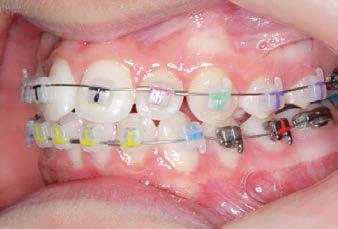

FINAL - 10/10/19 - Appliances removed AFTER

PROGRESS 7 - 10/10/19 - Final day in SLX 3D Clear Brackets BEFORE